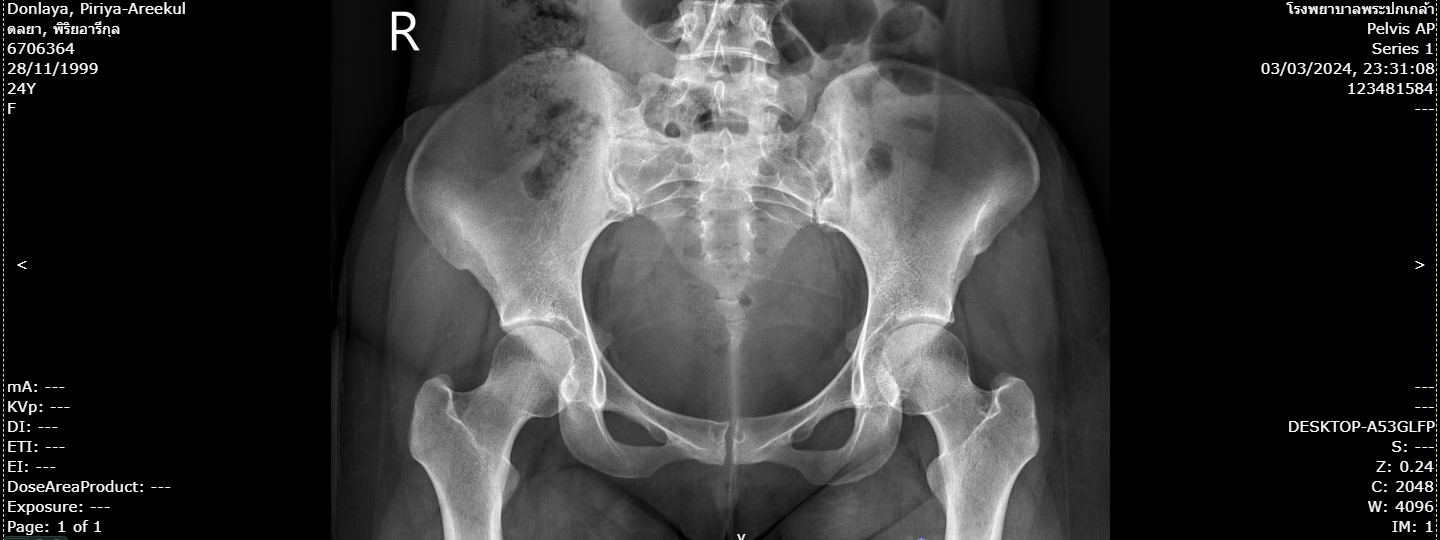

265ดลย.jpg                                   19-Apr-2024 08:03              128546